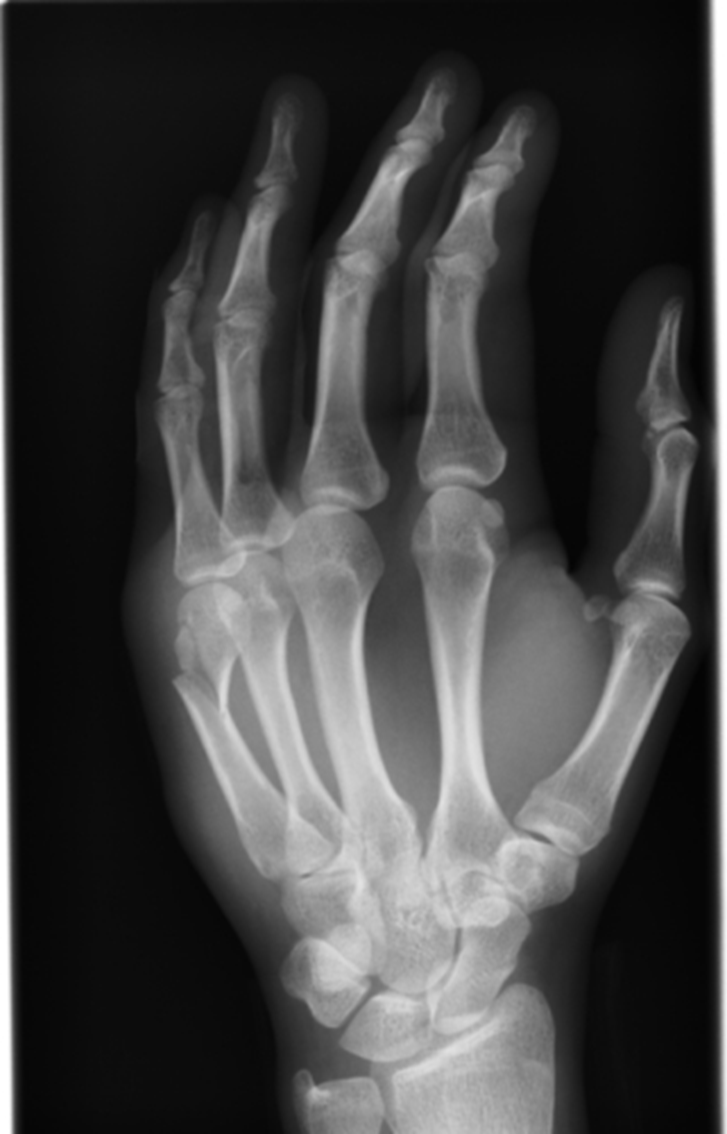

What view is this

PA hand